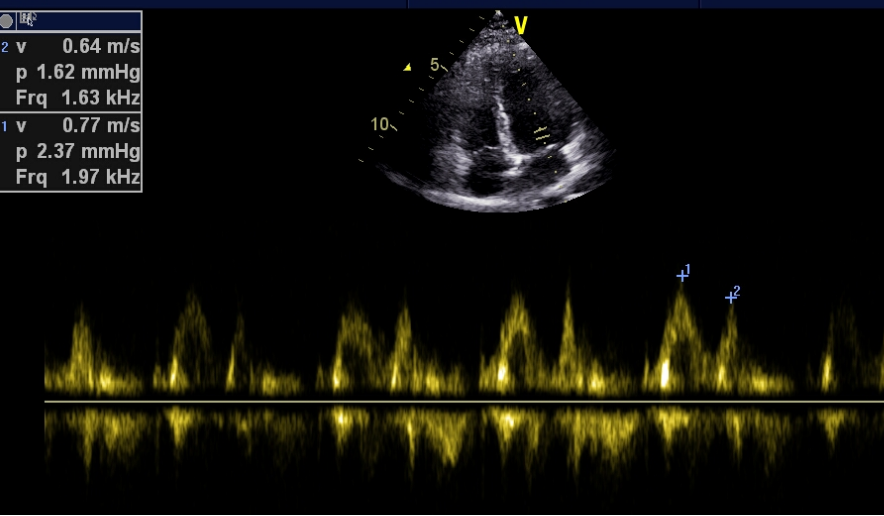

四、频谱多普勒型超声:脉冲波多普勒或连续波多普勒超声。

1.PW(脉冲波多普勒)

彩超logiq怎么读B超、彩超“傻傻分不清楚”?其实区别就在这!_https://www.jmylbn.com_新闻资讯_第8张

工作原理:应用多普勒效应,检测人体组织、器官的血流信息。与二维图像相结合能做出更准确的诊断。分为脉冲多普勒(PW)和连续多普勒(CW)。

应用范围:判断血流方向、判断血流性质;测定血流速度及压力阶差;评价心脏功能;检测异常分流、反流。

2.CW(连续波多普勒)

定量估测分流量及反流量;估测各房室腔内的压力;通过多普勒信号声调,估测血流性质、血流速度等。